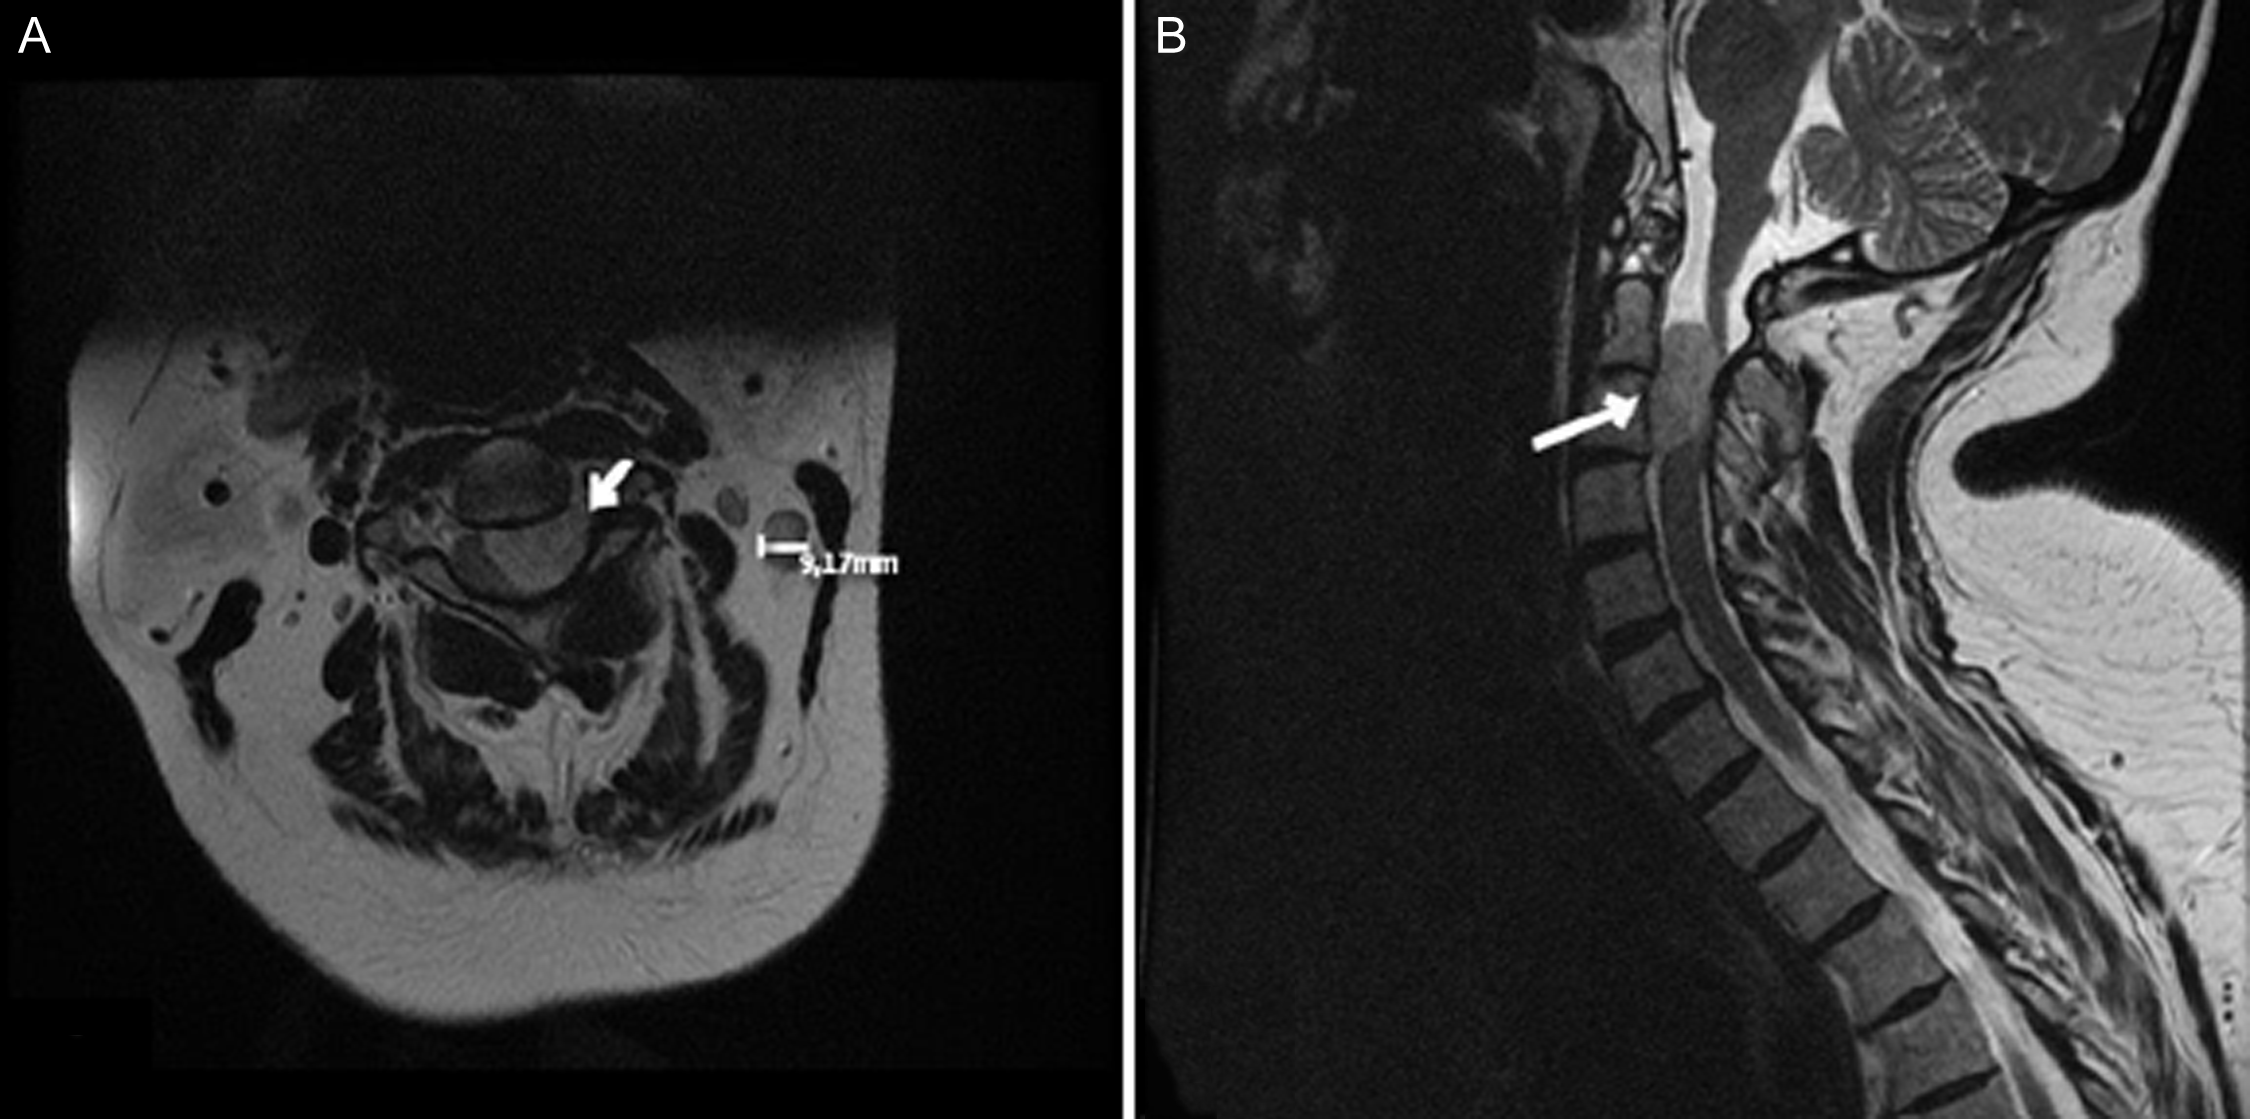

A 56-year-old female presented to our department with left upper extremity neuropathic pain accompanied by left-sided weakness (Table 3). Imaging revealed C2 – C3 lesion with a craniocaudal diameter of 2.9 cm (Figure 2). Intraoperative bony resection, dural opening and tumour exposure are illustrated in Figure 3. Surgery was performed as described in the Methods section. Intraoperative neuromonitoring confirmed proper neurological function. Post-operative imaging confirmed GTR, adequate spinal cord decompression with preserved joint integrity and spinal stability (Figure 4). The patient experienced no surgical complications and was discharged home on post-operative day 2. At 12-month follow-up, no tumour recurrence was reported (Table 4).

Figure 3. Patient 1 intraoperative imaging. (A) Lamina exposure. (B) Dural opening (C) Tumour exposure and debulking. Image obtained with permission from the patient.